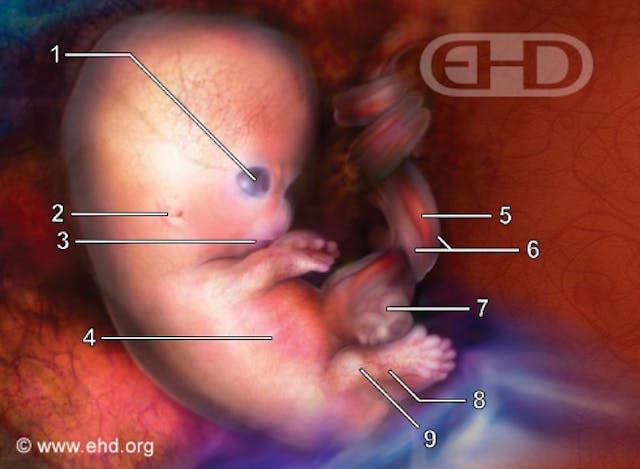

As you can see in the image below, taken from The Endowment for Human Development (a site unaffiliated with the pro-life movement), a preborn baby has arms and legs, complete with fingers and toes, very early on in pregnancy. This baby is 7 ½ weeks old (dated from conception).

By eight weeks, the preborn baby is fully formed. At this time, she has a brain that is divided into cerebral hemispheres, just like an adult’s. The preborn baby’s brain has been generating brain waves since six weeks. Her heart has been beating since 22 days. It is nearly impossible to look at an eight week preborn baby and not realize she is a developing human. The baby certainly doesn’t look like a cat fetus or a dog fetus – she has a human form.